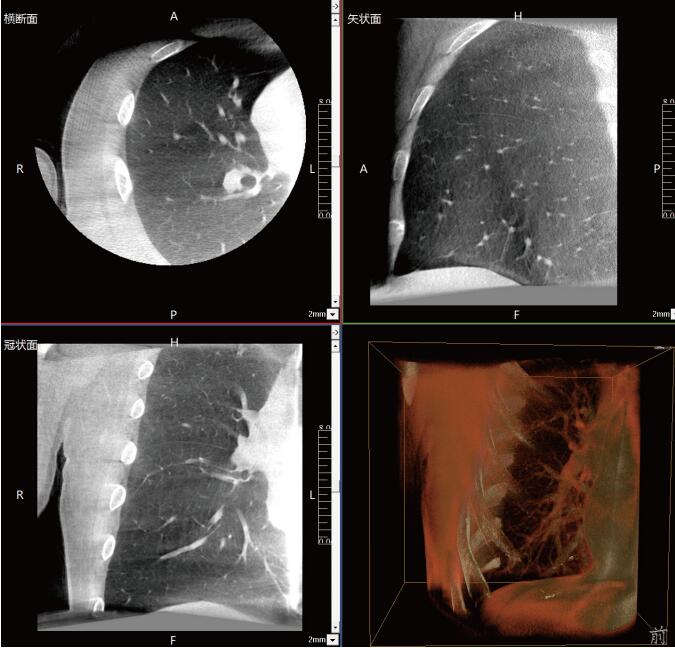

呼吸介入C型臂臨床應用-普愛醫(yī)療三維C型臂CT產(chǎn)品說明:

近年來,在肺部手術領域的應用呈現(xiàn)出顯著的增長態(tài)勢。這一技術不僅滿足了臨床指導穿刺、精準確認病變與針尖位置關系的迫切需求,更通過大量臨床研究的驗證,證明了其在肺結節(jié)診斷、定位及治療中的有效性和安全性。

《中國專家對CBCT引導下肺結節(jié)的診斷、定位和治療的共識》提到C型臂CT系統(tǒng)憑借其強大的功能,能夠充分滿足透視監(jiān)測、病變與工具位置確認、消融區(qū)監(jiān)測以及并發(fā)癥檢查等多元化的臨床需求。因此,在考慮設施條件(如導航設備、手術室空間)、靶病灶特性(大小、密度)、麻醉方法及干預路徑(經(jīng)支氣管或經(jīng)胸)等多重因素的基礎上,C型臂CT系統(tǒng)成為了眾多醫(yī)療機構的優(yōu)選方案。

呼吸介入C型臂CT的臨床適應癥廣泛,包括支氣管鏡檢查、肺結節(jié)穿刺活檢、肺結節(jié)定位、肺結節(jié)消融以及經(jīng)支氣管肺結節(jié)診療等多個領域。其臨床應用價值不言而喻:在經(jīng)支氣管干預肺結節(jié)時,透視功能可精準引導支氣管鏡與活檢鉗直達靶結節(jié);重建的三維圖像則能清晰展示干預工具的位置,確保操作的準確性。在肺結節(jié)消融過程中,呼吸介入C型臂CT更是實現(xiàn)了高精度定位,有效提升了治療效果。